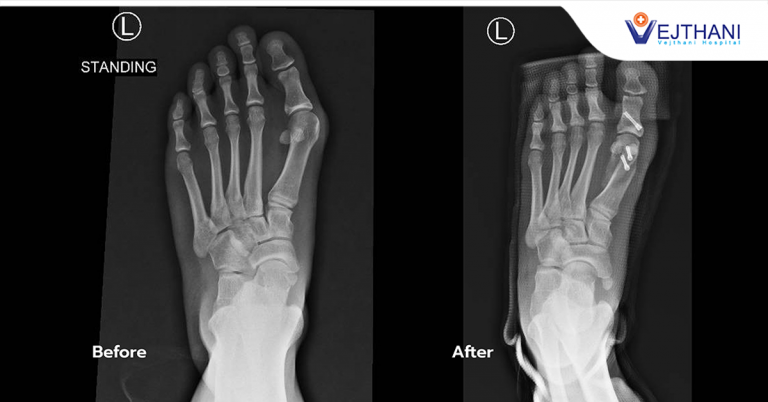

Beauty is Pain: “Toe Deformities” could be a Silent Threat to working People

Did you know that women tend to have a higher risk of “toe deformities” than men by 13 times? The majority of the working women wear leather shoes to work for 6-8 hours per day, developing pain in the inner part of the toes. Notice the painful toe from a round swollen bump on one side. For some people, it can be noticed that the big toe has been visibly deformed.